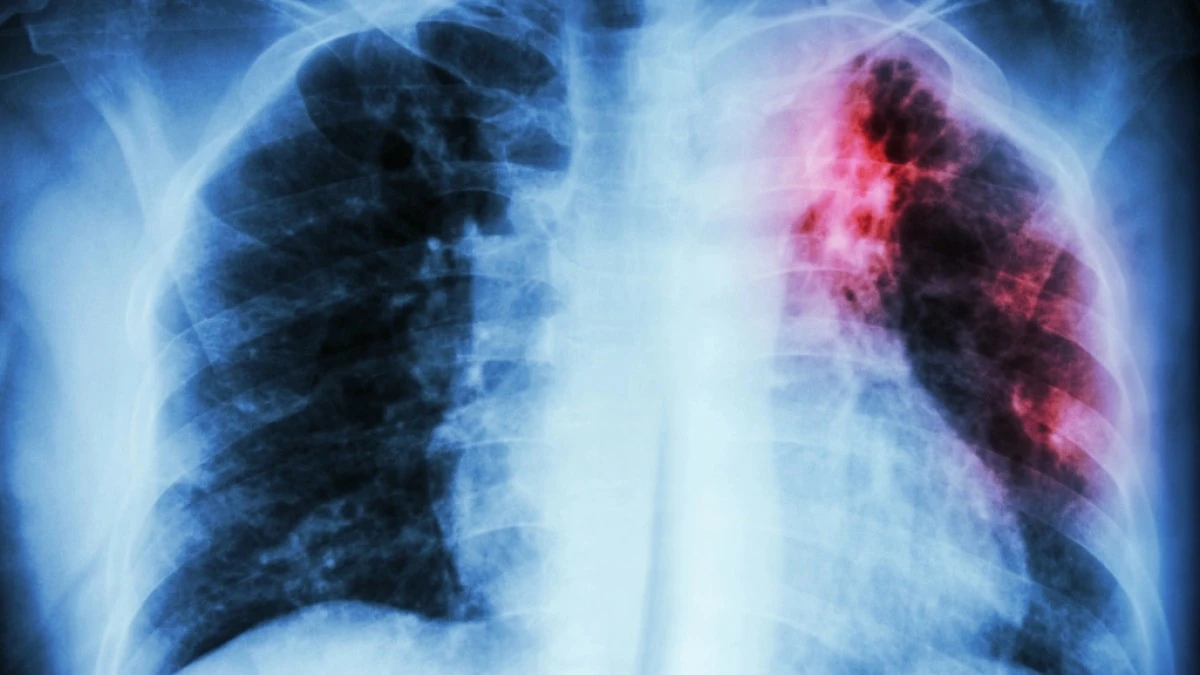

В Северо-Казахстанской области у школьника открытая форма туберкулёза: родители просят дистанционку, но школу не закрывают, сообщает Malim.kz со ссылкой на pkzsk.info.

В селе Новоишимское Северо-Казахстанской области у шестиклассника средней школы № 1 выявлена открытая форма туберкулёза. Ребёнок госпитализирован, в образовательном учреждении проведена дезинфекция и продолжается медицинское обследование всех контактных. Родители обеспокоены и просят временно перевести детей на дистанционное обучение, однако школа продолжает работать в обычном режиме.

Как стало известно, заболевший мальчик уже проходил лечение от туберкулёза в 2021-2022 годах. Новый случай — это рецидив.

"12 мая в департамент поступило экстренное извещение из районного управления о том, что выявлен случай заболевания туберкулёзом у ученика 6 класса Новоишимской школы № 1, — сообщил заместитель руководителя департамента санитарно-эпидемиологического контроля Северо-Казахстанской области Арман Кушбасов. — Это рецидив. В 2021 году ребёнок заболел, в 2022 году завершил лечение. Но поскольку в лёгких оставались изменения, риск повторного заболевания сохранялся".

"Детям проводят реакцию Манту, подросткам старше 15 лет и взрослым — флюорографию. В классе уже обследованы 17 человек. Через три дня проанализируют снимки, после чего станут известны предварительные результаты, — пояснил заместитель руководителя областного департамента санитарно-эпидемиологического котнроля. — Контактные наблюдаются от нескольких месяцев до 2 лет в зависимости от индивидуальных показателей. Главное — не отказываться от обследования".

Фото: gesund.bund.de